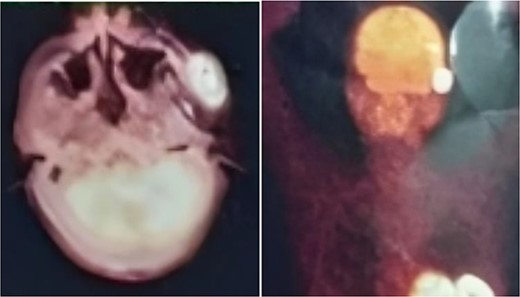

A 57-year-old male was referred to the urology department with hematuria 6 months before. Computed tomographic (CT) showed a mass in the bladder without any other significant results (Fig. 1). Endoscopic examination showed a solid lesion within a large diverticulum where biopsies were performed and the histopathology examination showed UC (invaded the lamina propria, pT1). A radical cystectomy with ileal conduit was performed with extended pelvic lymph node dissection. The histological study indicated the presence of a high-grade UC, which invaded the muscularis propria to the perivesical fat (Fig. 2) with neural and lymphovascular invasion (Fig. 3), but the metastases to pelvic or obturator lymph nodes were absent. After that, he received adjuvant chemotherapy (Paclitaxel), but he could not tolerate the side effects of the drug, which led to the cessation of treatment after only two doses. Two months later, he complained of swelling on the left cheek (Fig. 4) with pain in the left shoulder. Positron emission tomography and CT (PET-CT) showed an unclear, heterogeneous mass that leaches into the skin and adipose tissue underneath it and the left masticatory muscle measuring 40 × 20 mm showing pathological metabolic activity (Fig. 5). In addition to the presence of osteolysis in the posterior arch of the left eighth rib with the formation of a tissue mass extending over 75 × 35 mm showing pathological metabolic activity. Surgical intervention was performed to remove the described masses, and the histological examination demonstrated the presence of UC. Then, he received chemotherapy (Paclitaxel, 6 doses), and unfortunately PET-CT showed a relapse which occurred 4 months later, where the eighth rib was removed and supraclavicular region. Then, he underwent immunotherapy (Nivolumab) and radiation therapy until his death 10 months after the first appearance of cheek metastasis. There was no recurrence in place of the removed mass on the cheek.

PET-CT demonstrating an unclear, heterogeneous mass that leachates into the skin and adipose tissue underneath it and the left masticatory muscle measuring 40 × 20 mm showing pathological metabolic activity.